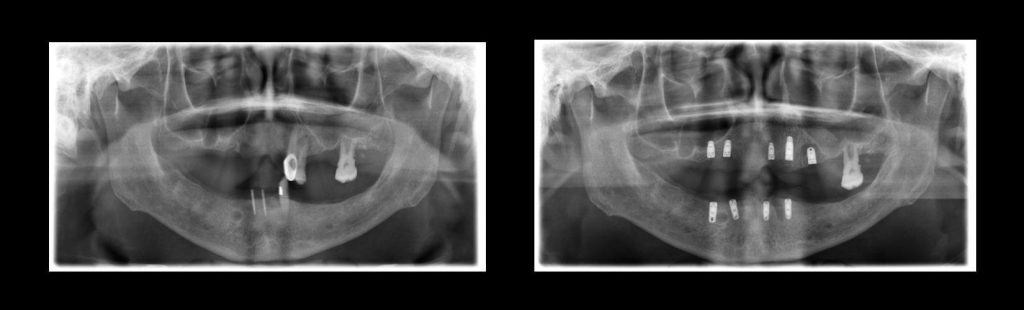

Case Study: Porcelain Veneers & Crowns

Our porcelain veneers and crowns are designed to correct a wide range of dental concerns — from discoloration and staining to chips, gaps, and uneven teeth. Each case is unique, but the results are always the same: a natural, radiant, and confident smile.

Before: Patients came to us with stained, worn, or misaligned teeth that affected their confidence and ability to smile freely.

Treatment: Using advanced digital smile design, we crafted custom porcelain veneers and crowns tailored to each patient’s facial features and expectations.

After: Bright, even, and youthful smiles that look natural and restore self-confidence in both personal and professional life.